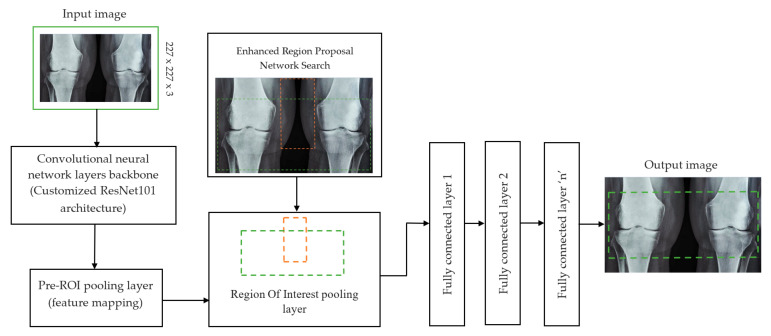

The initial step involved reducing an image to a size of 227 × 227 × 3. We used two convolutional neural networks for RA detection and classification in the second phase (Hybrid ResNet101 and VGG16). The image characteristics must be sufficient for accurate CBD grade determination and effective RA classification. We identified marginal joint space narrowing and categorized RA using these convolutional neural networks to extract instructive visual characteristics. To complete the RA classification process, two CNNs were used. First, we used ResNet101 with a domain adaptation strategy to identify marginal joint space contraction. Second, we used VGG16, which was trained using a domain adaptation technique, to classify RA. Finally, we evaluated the method’s effectiveness and contrasted our findings with those of other similar techniques already in use. Figure 1 shows a flowchart of the recommended process.

In deep learning, the F-CRNN is just one of the methods. The faster CRNN architecture is now the standard object identification method because of its ability to anticipate and score single or numerous items in an image. The enhanced-region proposal network and F-CRNN are two integral parts of the F-CRNN network. To ensure that the Quick R-CNN module receives only the best region suggestions, the ERPN generates them. To identify areas of interest in digital X-radiation pictures, we trained the ERPN. The end-to-end convolutional network (ERPN) can accurately anticipate the boundaries and scores of objects of interest at any coordinate. The ResNet101 network was used for F-CRNN feature extraction.

Each convolutional layer in ResNet101 was followed by a batch normalization and activation layer (ReLU). By avoiding parallel connections to the typical layers, this architecture facilitated more efficient training of deep neural networks. Features were extracted, and convolutional feature maps were generated using a combination of convolutional and max-pooling layers. Image characteristics were fed into ERPN, and region suggestions were generated as outputs. The ROI pooling layer took the feature vectors from the function maps. Each vector function was linked to the underlying layer. We individually trained the ROI detection model for the AP view’s medial and lateral compartments. When the algorithm produced several ROI detections, we chose the ROI with the highest prediction accuracy for each knee joint. To evaluate the proposed model, we counted the narrow regions of the marginal joint space that achieved IoU ≥ 0.70. As a result of the detection, we saved the predicted bounding boxes. We used weights that had already been trained on ResNet-101, and then used the domain adaptation method to fine-tune them. Figure 2 shows how modified ResNet-101 can find approaches with a narrow joint space in the knee. The most important part of the Faster R-CNN architecture is ERPN. ERPN predicts the scores of objects and their locations. The algorithm compares the narrow areas of the knee joint space in the medial and lateral compartments to find the narrow area in the middle. The best thing about this method is that it can find even the smallest changes in knee joint space.